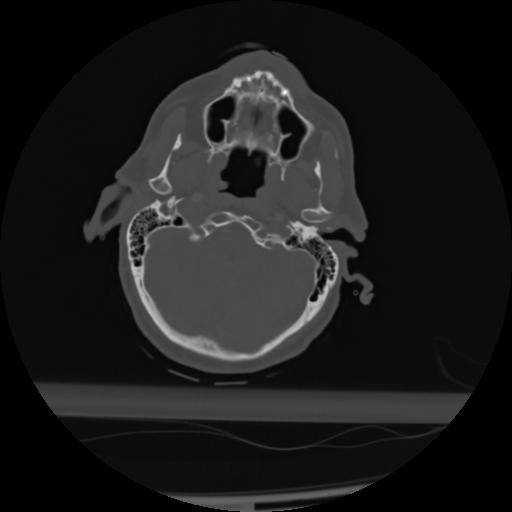

21 ANGIO,CE,Axial,3.0,ANGIO,,